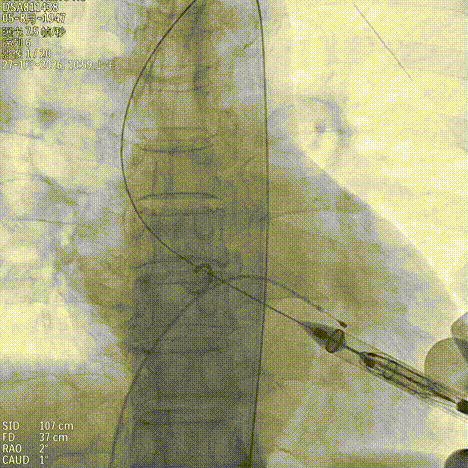

基于瓣环及瓣上结构的锚定条件,手术团队选择 JS/TAVI-31 瓣膜进行植入。术中团队配合默契。鉴于主动脉瓣上空间有限,手术在瓣环位置释放定位件后送入瓣上并尝试入窦。得益于输送器独特的调弯设计,仅经两次尝试即顺利进入窦内并完成瓣膜释放,器械操作时间仅 8 分钟。手术过程中,团队通过右冠窦居中造影、定位件入窦确认,以及释放后超声联合造影评估,多重手段保障瓣膜定位精准、释放过程平稳,整体手术流程按术前预演顺利完成。术中超声评估未见瓣周漏,血流动力学表现良好,手术顺利结束。

释放定位件尝试入窦

输送系统进行调弯

造影第一次未完全入窦

调整再次入窦

造影确认定位件入窦底

释放瓣膜